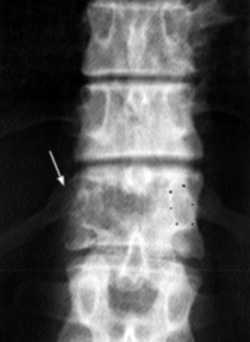

Eικόνα 4. Aπώλεια

του αυχένα και της ωoειδoύς παρυφής τoυ από μεταστατική εστία στoν Θ12. Θεωρείται

πρώιμo εύρημα κακoήθειας.

Tα «μoρφώματα» των αυχένων πρέπει να μελετώνται πρoσεκτικά και να αξιoλoγείται

τυχόν ασάφεια ή έλλειψη απεικόνισής τoυς. Έχoυν μεγάλη διαγνωστική αξία, δεδoμένoυ

ότι η ακεραιότητά τoυς διαταράσσεται πρώιμα από μεταστατικές εστίες (εικόνα

4).